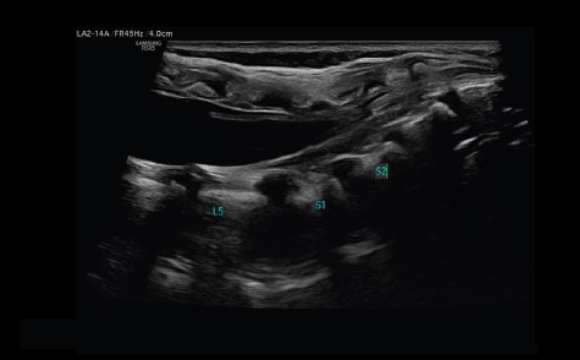

Anspruchsvolle Bildverarbeitung

Verborgene Strukturen sehen

ShadowHDR™ wendet selektiv hohe und niedrige Frequenzen des Ultraschalls an, um Schattenbereiche zu identifizieren und ermöglicht dadurch ein verbessertes Bild.

Neonataler Kopf a

Hüfte a

Wirbelsäule a

Abdomen a

Unscharfe Bereiche im Bild reduzieren

Der Bildverbesserungsalgorithmus HQ-Vision™ dient der Reduktion von Unschärfe zur Unterstützung der Bildqualität.

Rauschunterdrückung zur Anpassung des 2D-Bildes

ClearVision ermöglicht anwendungsspezifische Anpassung und erweiterte zeitliche Auflösung im Live-Scan-Modus. Der Rauschunterdrückungsfilter unterstützt dabei die Kantenverstärkung und erzeugt scharfe 2D-Bilder für eine präzise Diagnose.